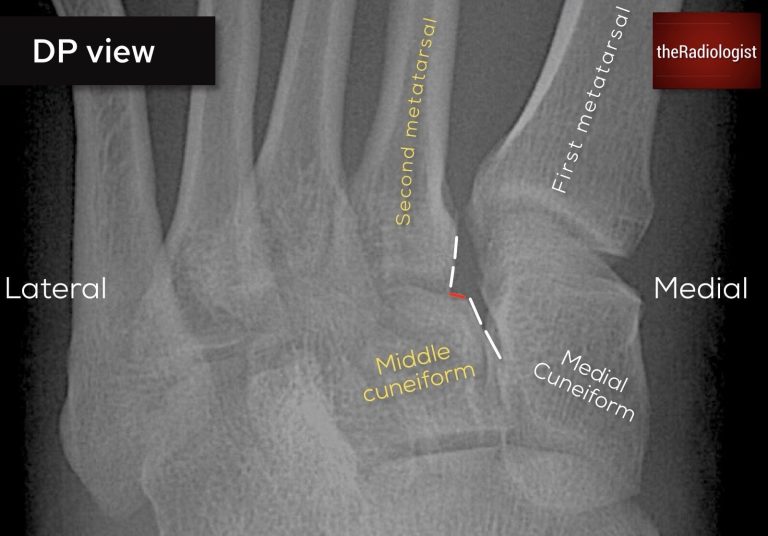

• DP view: the lateral borders of the 1st metatarsal and medial cuneiform should line up.

• DP view: the medial borders of the 2nd metatarsal and middle cuneiform should line up.

• Oblique view: the borders of the third metatarsal should line up with the lateral cuneiform.

To check the alignment it is really important that you zoom up and check the bones line up completely! Have a look at the X-Rays below for examples.

Typically you will see an increased gap between the 1st and 2nd metatarsal with lateral displacement of the base of the 2nd metatarsal. You may see flecks of bone at the 2nd metatrsal base, or around the 3rd metatarsal or cuneiforms.

Looking for Lisfranc injury (DP view): on a DP view the lateral borders of the medial cuneiform and first metatarsal should line up as well as the medial borders of the second metatarsal and middle cuneiform

Looking for Lisfranc injury (DP view): in this case there is a subtle step between the middle cuneiform and the second metatarsal – this is a Lisfranc injury.